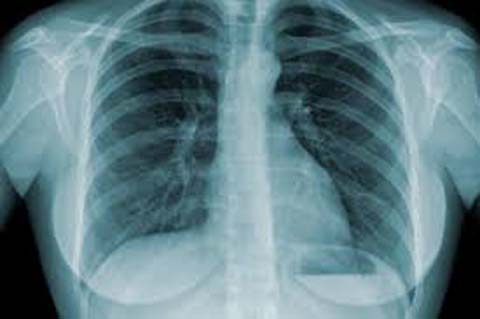

Dia Mundial da Tuberculose alerta sobre tratamento da doença

A tuberculose continua a ser a segunda principal causa de morte por doença infecciosa na América, depois de HIV e Aids. Apesar dos progressos significativos no seu controle o Ministério da Saúde (MS) informou que muitos pacientes ainda deixam o tratamento na metade.

A tuberculose é causada pelo Mycobacterium tuberculosis, uma bactéria que afeta os pulmões com mais freqüência. Uma em cada três pessoas no mundo tem tuberculose latente, o que significa que eles estão infectados, mas não têm sintomas e doença ativa não pode transmiti-la.

A tuberculose é transmitida pelo ar quando as pessoas que têm a infecção tossem, espirraram ou cospem. Os sintomas da tuberculose pulmonar incluem a tosse de mais de duas a três semanas, perda de peso, febre, suores noturnos, perda de apetite e tosse com sangue. A doença é curável, mas pode ser fatal se não tratada. O tratamento geralmente dura seis meses.